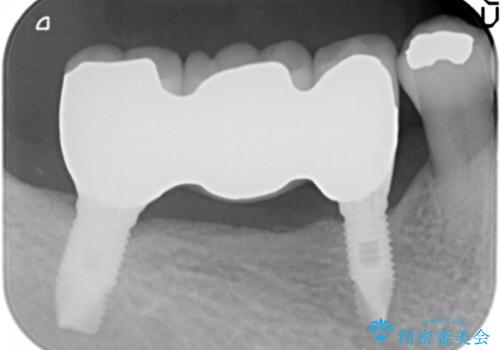

なるべく予算を抑えたいとのご希望から、上顎は入れ歯、右下臼歯部はインプラントによる治療を行いました。

しっかりと咬むことができるようになり喜んで頂けました。

全体的な歯の動揺もなくなり安心して頂けました。

4年経過しましたが問題なく調子が良いとおっしゃって下さいました。

左下のインプラント治療もご希望され、現在治療中です。

被せ物の種類:メタルボンドクラウン エコノミー

インプラントの種類:スプラインツイスト